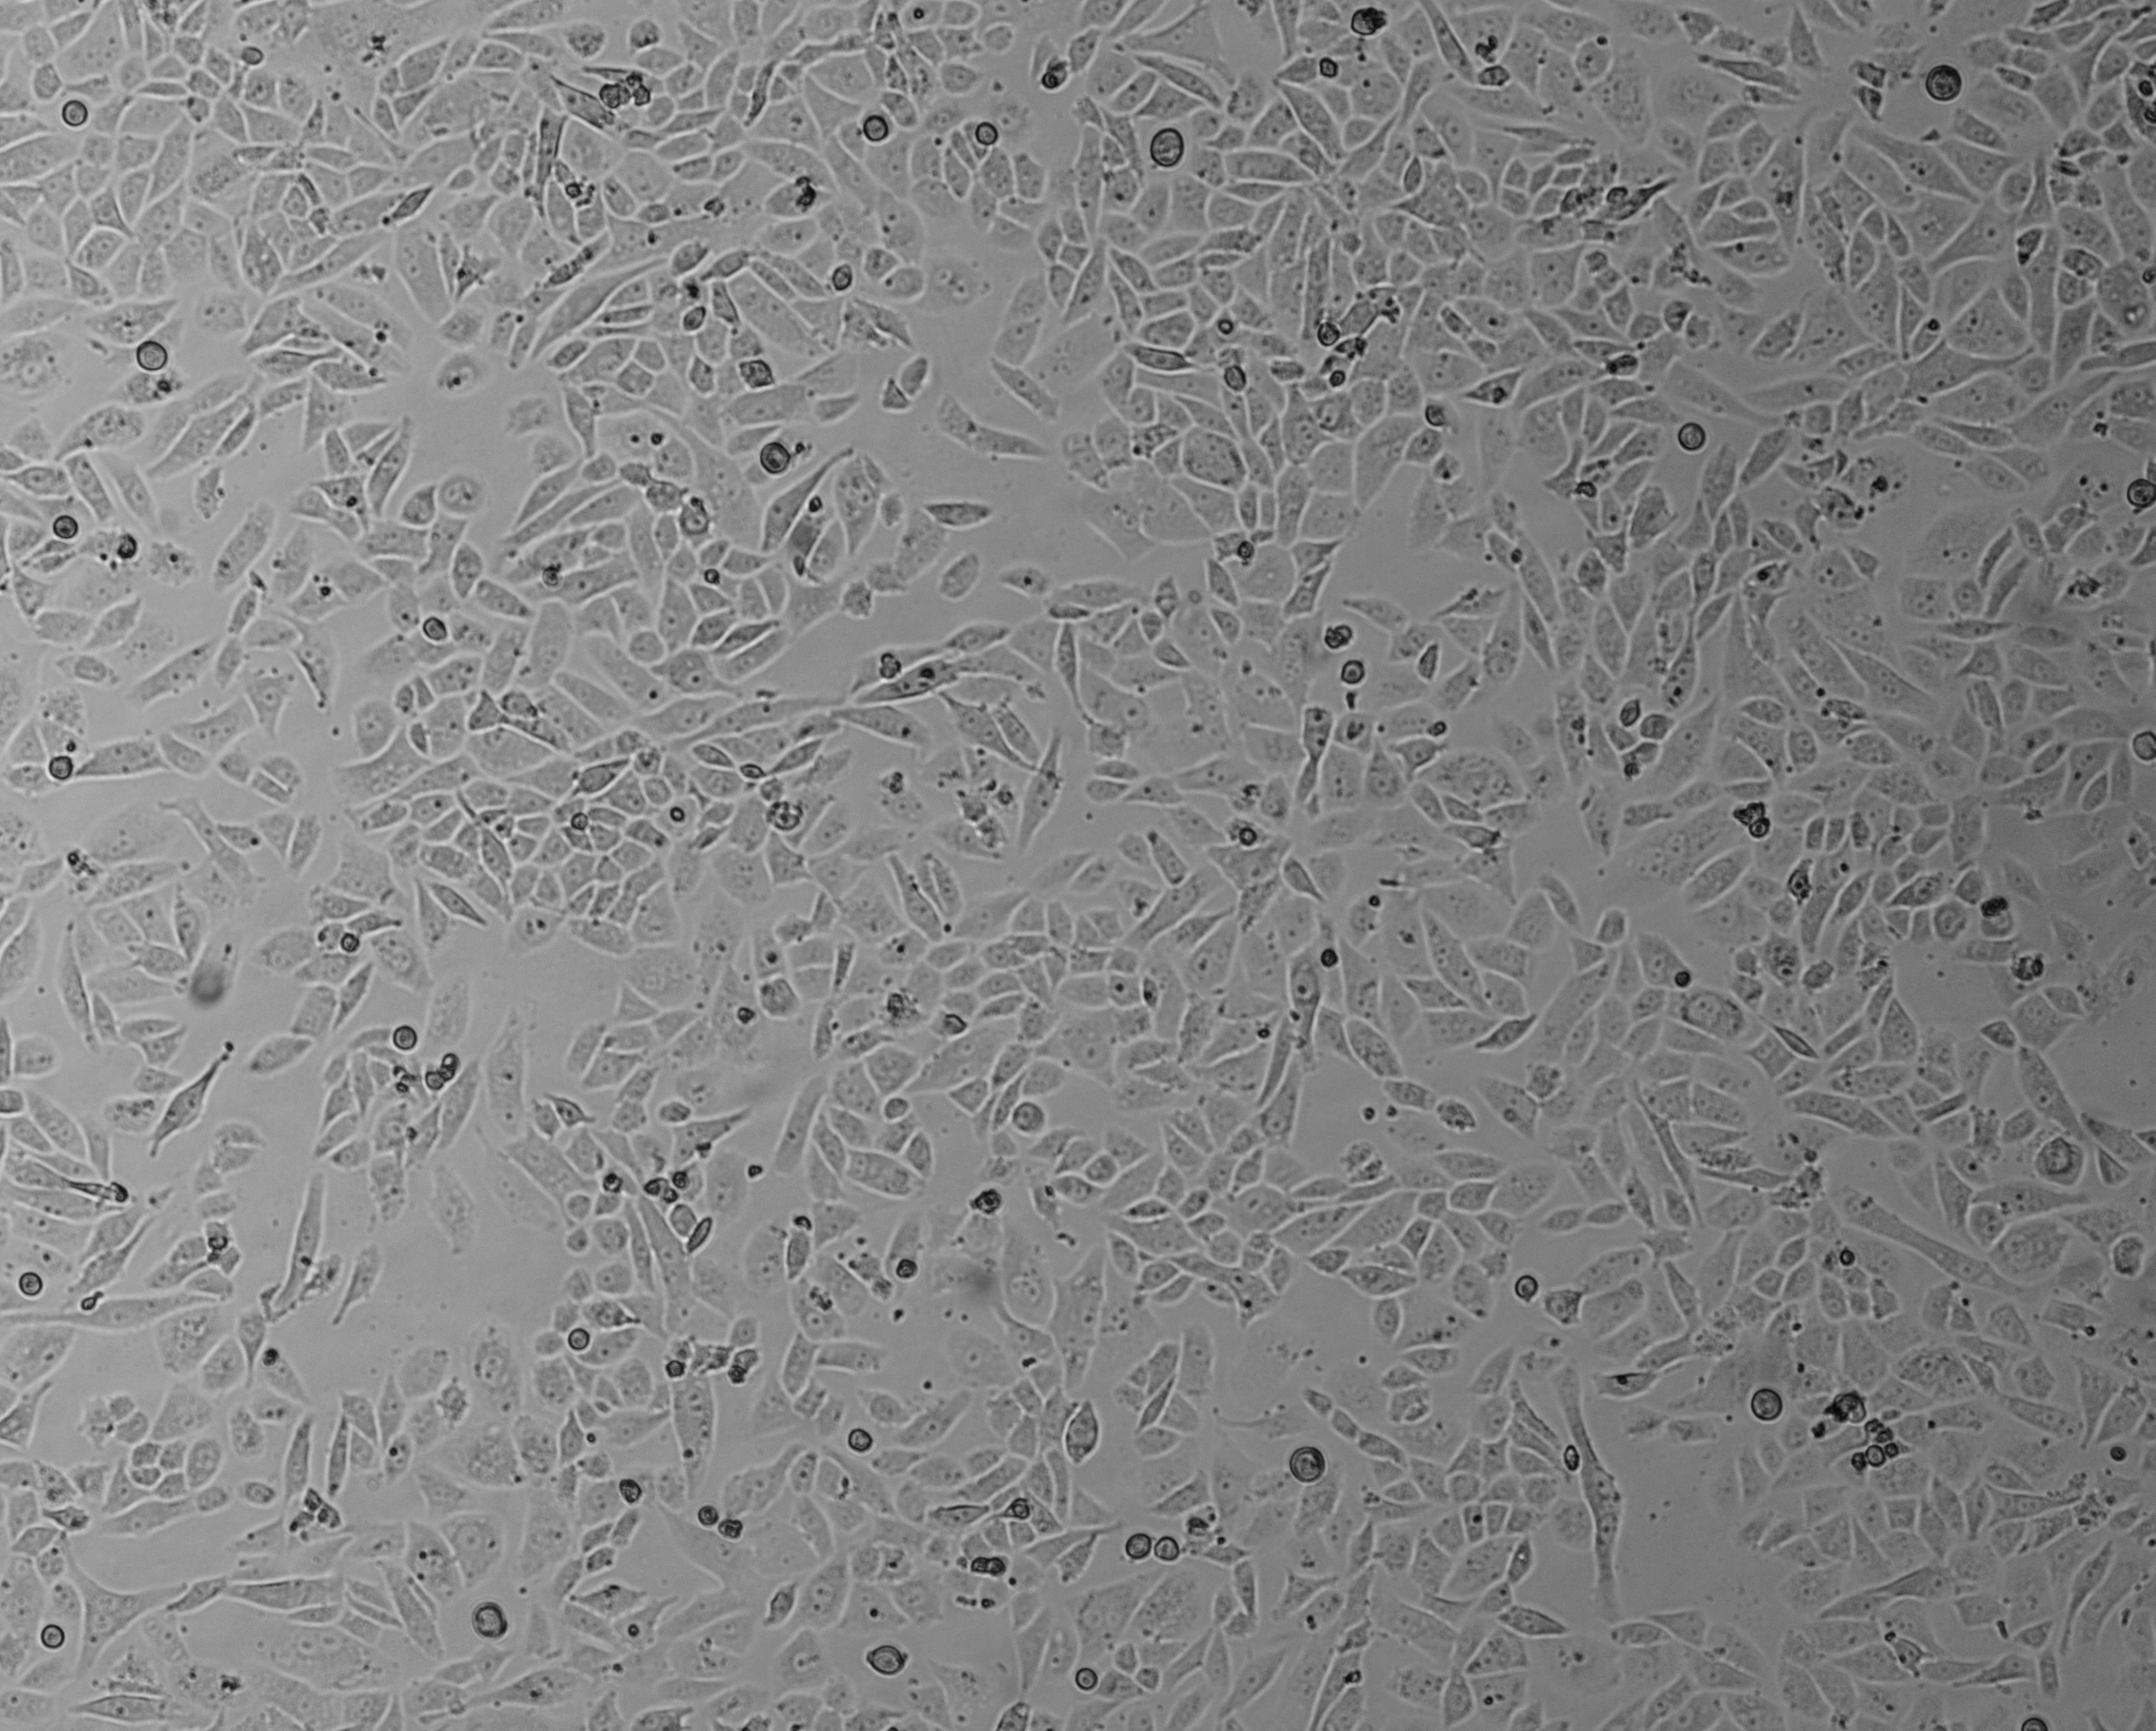

细胞攻略 | SW480(人结肠腺癌细胞)培养教程

细胞简介: SW480 [SW-480]细胞源自50岁Dukes C结直肠癌白人男性患者原位直肠腺癌,后来SW620细胞源自同一病人一年后的淋巴结转移。SW480 [SW-480]细胞表达EGF, CSAp和直肠抗体3阴性,角蛋白阳性。SW480 [SW-480]细胞p53基因第273位密码子的G→A突变引起Arg→His替代,309位密码子的C→T突变导致Pro→Ser替代。SW480 [SW-480]细胞高水平表达p53蛋白,癌基因c-myc、K-ras、H-ras、N-ras、myb、sis和fos的表达呈阳性,癌基因N-myc的表达未做检测,不表达Matrilysin(一种与肿瘤侵袭相关的金属蛋白酶)。有报道称,SW480 [SW-480]细胞表达GM-CSF。SW480 [SW-480]细胞ras原癌基因的12位密码子有一个突变,可以用作PCR法检测该突变的阳性对照。1978年11月,A·Leibovitz将其提交给ATCC时已传代至第91代。SW480 [SW-480]细胞可以用于3D细胞培养和癌症研究,也是一种合适的转染宿主。